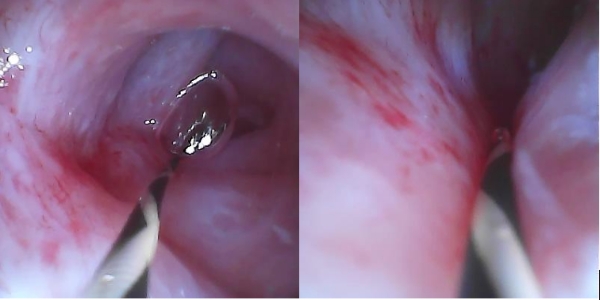

完成胰管取石后再次用胰管镜探查,胰管四壁未见乳头样或结节状新生物